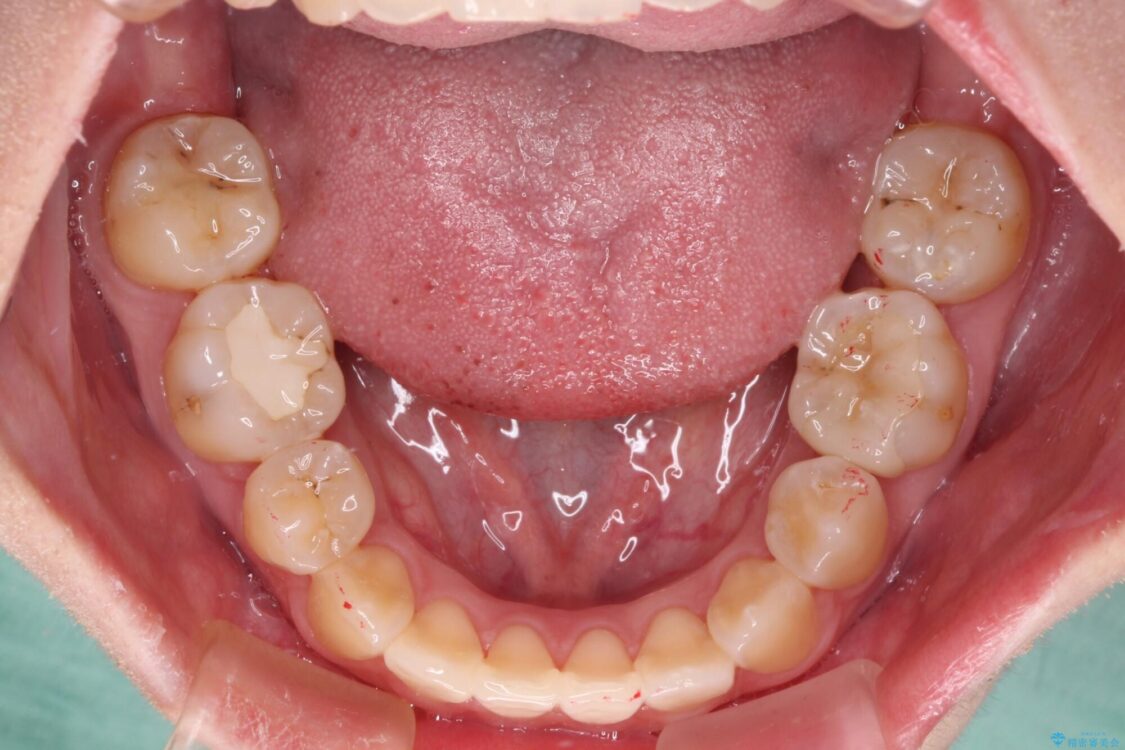

治療前

• 虫歯治療ついでに歯並びの後戻りを改善 インビザラインによる矯正治療 治療前画像

上顎親知らず周辺の炎症と、神経組織の失活した歯の炎症による痛みが認められたため、親知らずの抜歯と根管治療を行いました。

根管治療を行った歯はクラウンによる補綴治療が必要となりますが、高校生の頃に行った矯正治療の後戻りも気になるとのことで、補綴治療を行う前に矯正治療を行うこととしました。

後戻りは軽度であり、インビザラインにて歯列を整え、その後にオールセラミッククラウンにて補綴治療を行うこととしました。